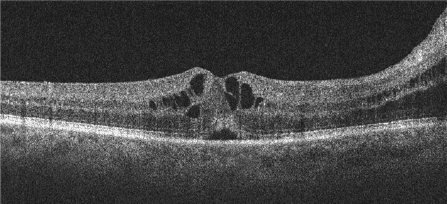

Fluid around the disc may also be related to choroidal neovascularization (CNV), which may cause SRF, IRF, hemorrhage and/or exudate. Whereas the serous aspects of fluid appear optically empty, hemorrhage appears more hyperreflective and heterogenous by OCT, and exudate is very hyperreflective (Figure 2).

Figure 2. Upper Panel: Juxtapapillary SRF with hemorrhagic pigment epithelial detachment and modest overlying subretinal hemorrhage due to CNV. Lower Panel: Juxtapapillary SRF with mid-retinal exudates due to CNV.